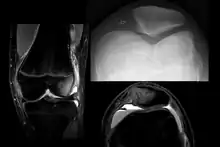

![]() | |

| X-ray showing a patellar dislocation, with the patella out to the side. | |